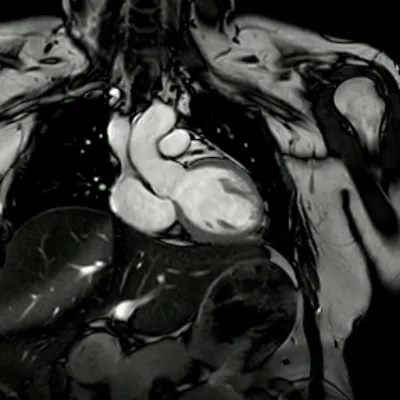

如今,心脏磁共振(MRI)检查就像一位自带高科技装备的 “心脏侦探”,凭借无辐射、高精度等超能力,成为诊断心脏疾病的 “王牌选手”。今天,我们就跟着国际权威指南和前沿研究,一起解锁它的五大 “超能力”!

二、高清 “透视眼”,不放过任何细节

软组织分辨率拉满

心脏 MRI 拥有一双 “火眼金睛”,它能将心肌、心包、瓣膜等细微结构看得一清二楚,甚至能精准区分正常心肌和病变组织,比如脂肪浸润、肿瘤等。就像在心脏里装了一台高清显微镜,帮助医生在早期就发现心肌病变的蛛丝马迹,为及时治疗争取宝贵时间。

全方位立体成像

这可不是普通的 “平面视角”!心脏 MRI 支持任意角度断层扫描,能从横断面、矢状面、冠状面等各个方向,全方位展示心脏的三维结构。遇到复杂先天性心脏病、心肌致密化不全等疑难病症,它就像一位经验丰富的侦探,抽丝剥茧,让隐藏的病灶无处遁形。